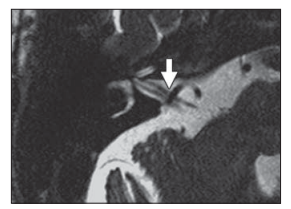

图10,T2相,面肌痉挛

患者可见血管压迫面神经,以小脑前下动脉多见